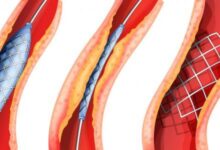

بالنسبة لأمراض الشرايين التاجيّة أو داء الشريان التاجيّ (بالإنجليزية: Coronary artery disease)، فإنّ الذبحة الصدريّة تُعدّ أكثر أعراض المرض شيوعًا، ويُعبّر عنها بالشعور بألم وضغط في الصدر أو ثقل أو حرقة فيه، إضفافةً إلى تنميل أو خدران غير طبيعي، كما يمكن أن يمتد الألم إلى أجزاء أخرى، مثل الكتف الأيسر، والذراعين، والرقبة، والفكين، والظهر، ومن الجدير بالذكر أنّ أمراض الشرايين التاجيّة قد تكون مصحوبة ببعض الأعراض الأخرى أيضاً،[٤] ومنها ما يأتي:[٤]

- التنميل، والضعف، والبرودة في الذراعين أو الساقين في حال تضيق الشرايين المسؤولة عن التروية الدمويّة فيها.